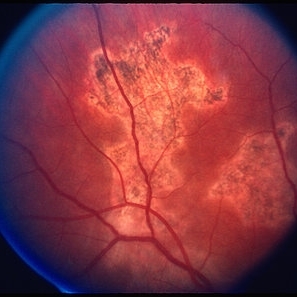

AIDS - Toxoplasmosis

Jun 4 2014 by Henry J. Kaplan, MD

Fundus photograph of a patient with AIDS who has developed toxoplasma retinochoroiditis; large yellow patch of retinitis along the superior arcade fading the vasculature with feathery edges. #1

Condition/keywords: AIDS, toxoplasmosis